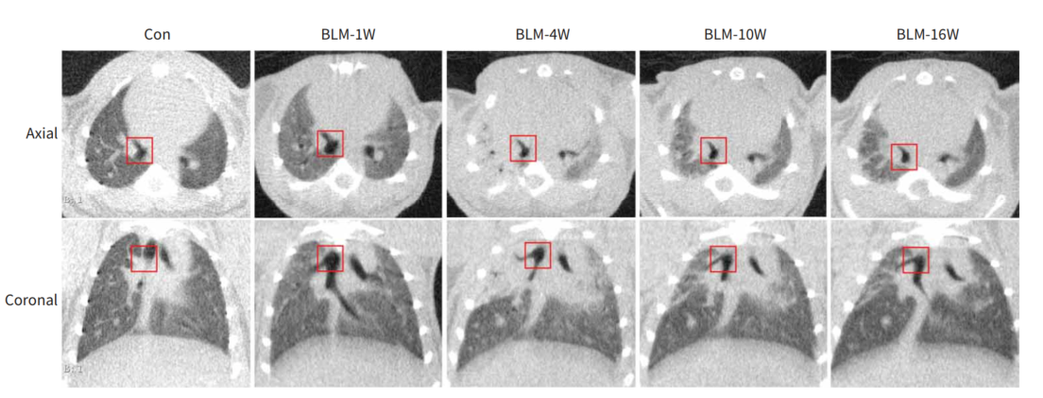

博来霉素诱导的小鼠肺纤维化模型。根据不同HU区间进行正常、低通气、不通气区域体积的分割。在第4周,结果显示低通气和不通气区域的比例都很高,然后在第10周和第16周之间明显减少,而在正常通气的区域,则呈现相反的态势。[13]

通过使用Micro-CT对小鼠肺部区域进行扫描重建成像,利用肺部分析算法(Hounsfield单位阈值范围分别为-434至-121HU和-120至121HU)实现对通气不良和非通气不良区域的影像区分,从而实现对肺部区域动态检测,并进行功能和结构的评价。量化的影像数据也能提供纵向研究的信息以减少动物之间的变异性,可以更进一步验证体外数据。

早期评估我们可以选择固定点(冠状面气管分支)位进行观察肺实质的变化,理应在造模第四周达到最大。

利用小鼠不同方式造模致其产生非小细胞肺癌肿瘤/肺腺癌/肺部纤维化,用药后在活体模型小鼠上,连续观察其肺部实质病变的变化,就可以来评价该药物的有效性。预期利用Micro-CT,可以同时实现活体小鼠造模是否成功的验证,以及通过对小鼠肺部长期连续性的观察来实现药物有效性的评估。